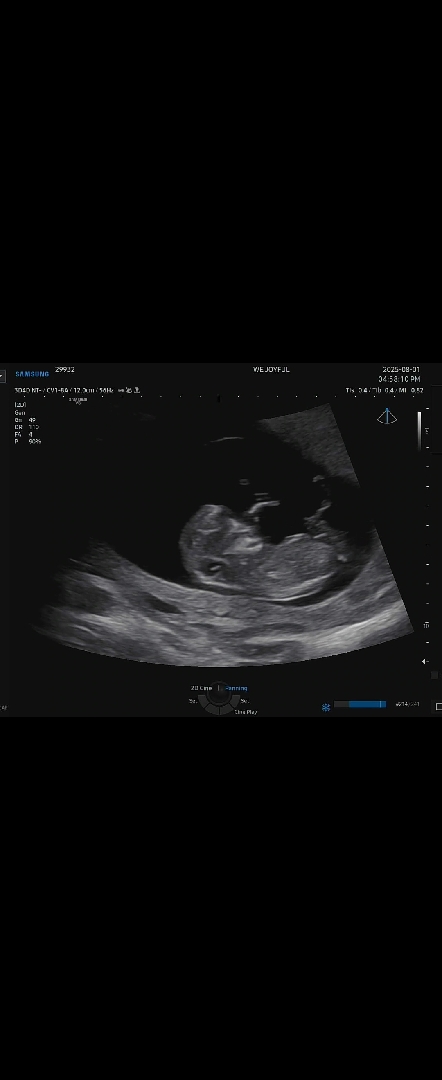

각도법무엇일까요

무엇같나요